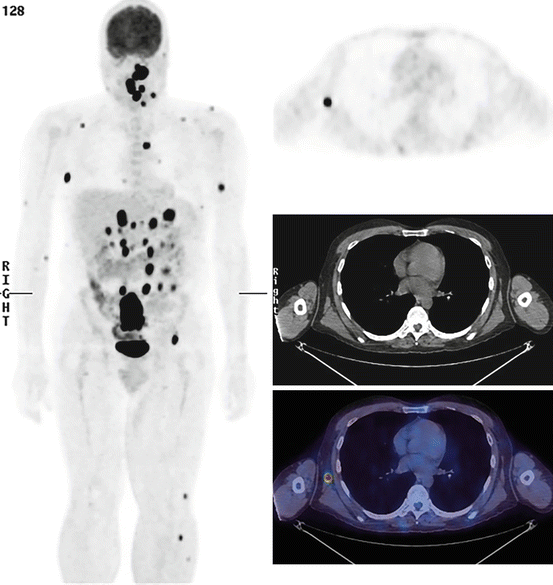

Stage IV metastatic melanoma, composite CT and PET scan Stock Image Pet Ct Scan For Melanoma Positron emission tomography (pet) scan. A pet scan can help show if the cancer has spread to lymph nodes or other parts of the body. Pet Ct Scan For Melanoma.